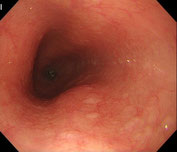

食道 |

胃 |

十二指腸 |